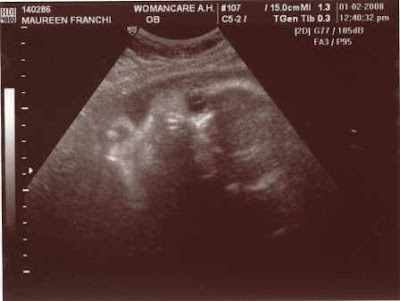

Baby Franchi - 32 Week Picture

Maureen and I had a great doctor's visit last week. Everything is going great with the baby. Strong on all accounts and measuring just as expected. We also had our most recent Ultrasound, so we wanted to share a picture with you.

This is a close up of the baby's face. Clearly a looker just like his or her parents...